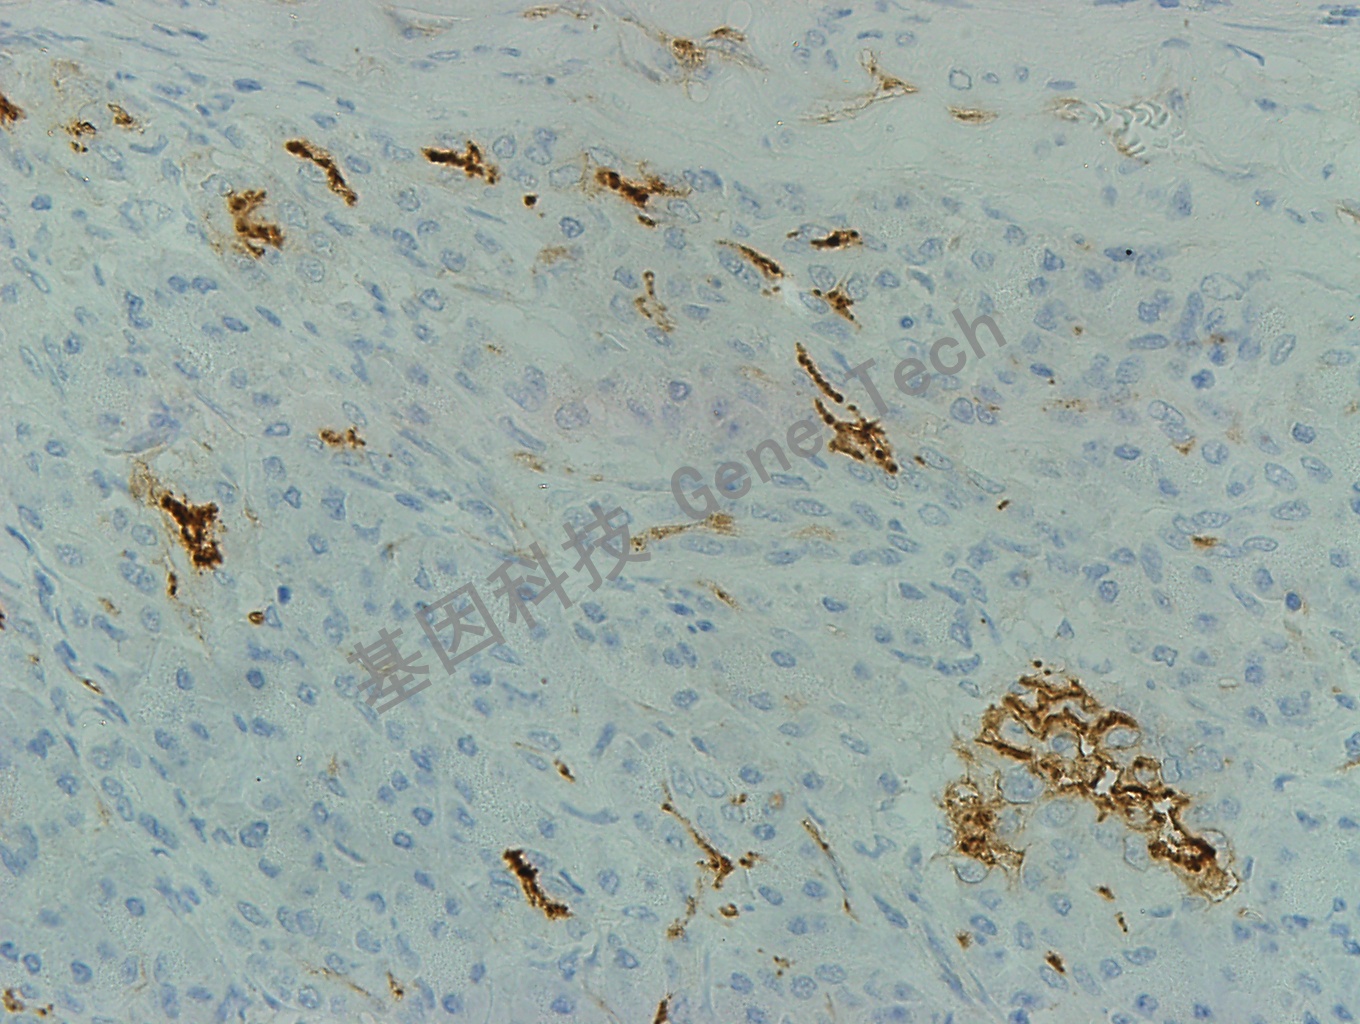

胰腺癌石蜡切片(10X),用 CD54(GT2254)染色,细胞膜阳性,DAB 显色。

胰腺癌石蜡切片(40X),用 CD54(GT2254)染色,细胞膜阳性,DAB 显色。